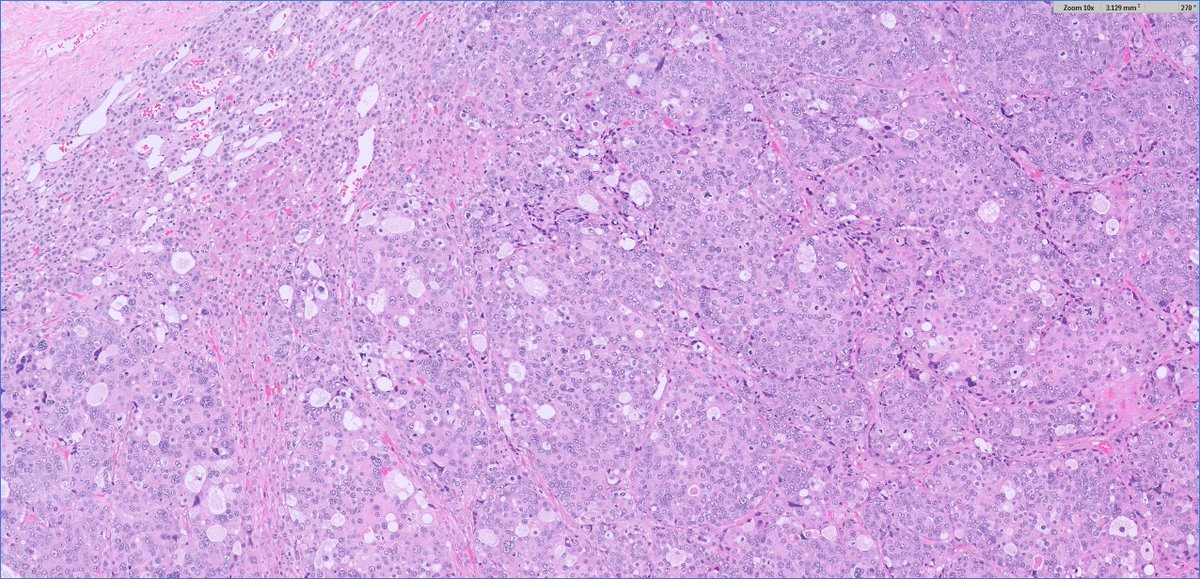

Q for the #endopath folks for this adrenal cortical adenoma (clinical: primary aldo) intratumor/adrenal fat I've seen, perhaps not all that uncommon... but intratumoral/adrenal brown fat? usually I see brown around the peripheral (within background excised fat) when it occurs

slusagar's tweet image. Q for the #endopath folks for this adrenal cortical adenoma (clinical: primary aldo)

intratumor/adrenal fat I've seen, perhaps not all that uncommon...

but intratumoral/adrenal brown fat? usually I see brown around the peripheral (within background excised fat) when it occurs